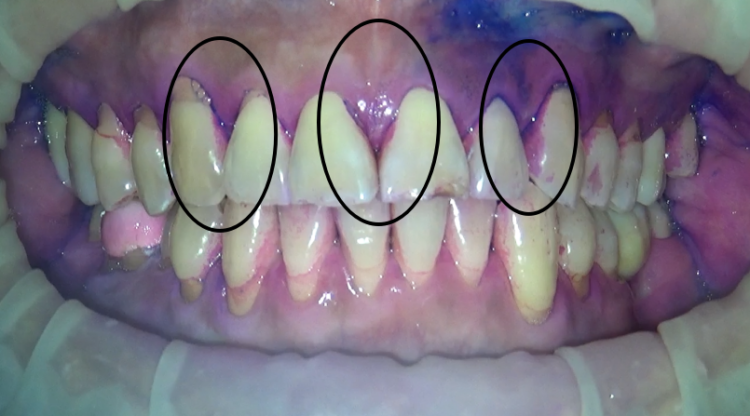

この方は、歯の表面はきれいに磨けいますね。歯周病の予防では絶対磨かなければならない、歯と歯茎の境目も磨けています。

ところが、歯と歯の間にプラークが残っています。

やっぱり、顕著に残ってしまいますね。

ということで、今回は、歯間ブラシとワンタフトブラシを使用していきます。

三か所、ピンポイントで磨いてみましたが、